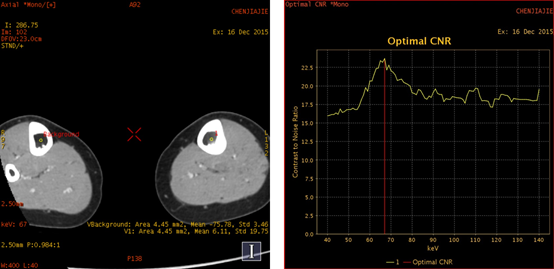

增强扫描 CNR 67kev最佳单能成像 增强扫描

随着单能量水平的减低,左侧胫骨髓腔内的病变显示更加明显; 低能量水平图像,可以很好显示小病灶以及轻微的强化病变。 左侧胫骨中段髓腔内转移